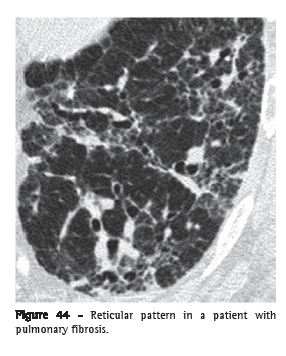

Reticular pattern (padrão reticular)

The reticular pattern is an alteration that is usually associated with interstitial diseases and is radiographically characterized by innumerable linear opacities that produce a net-like appearance.(1) On HRCT scans, it is possible to single out the components responsible for this radiographic pattern, usually related to the presence of interlobular and septal lines (Figure 44) or to the presence of cysts with walls giving the radiographic appearance of lines, such as in pulmonary cystic diseases, in bullae-related emphysema and even in honeycombing cysts.(1,3,7)